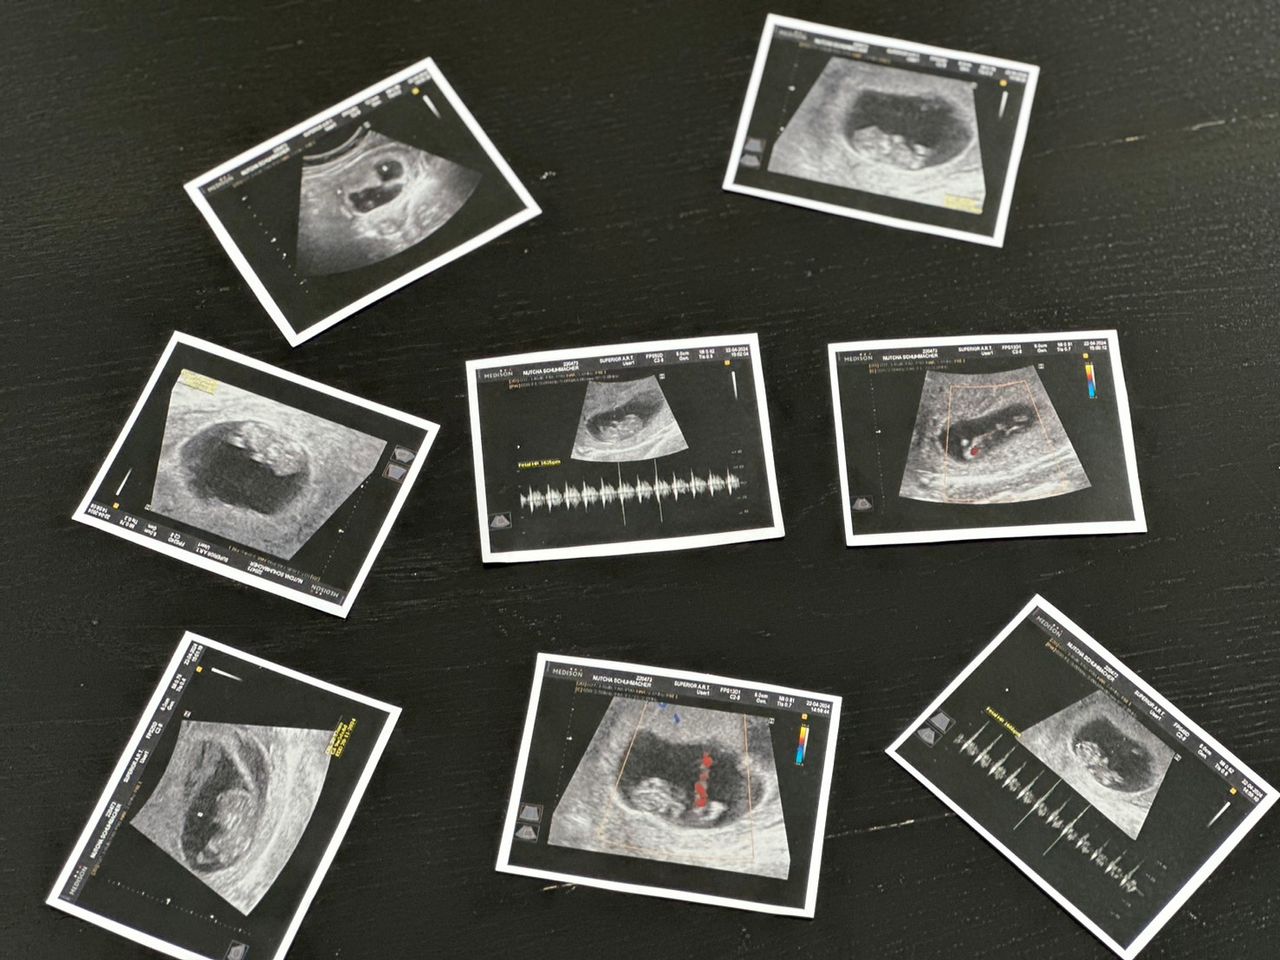

ที่ล่าสุดได้ลงรูปคู่ในไอจีในชุดสีขาวที่แอบให้เห็นท้องที่กำลังเริ่มใหญ่ขึ้น พร้อมประกาศข่าวดีว่าตอนนี้ นนนี่ กำลังตั้งท้องลูกคนแรกแล้ว และข้อความ "thank you for coming to my family. Love you baby #10weeks"